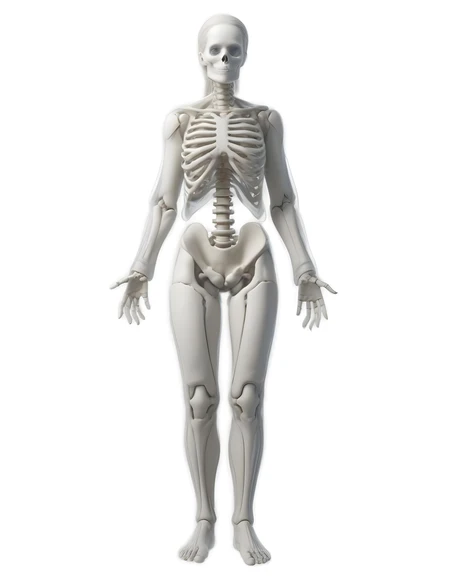

white woman skeleton

32 Photos